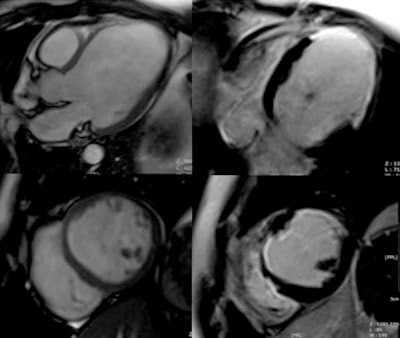

| MRI is leading to greater understanding of the mechanisms underlying cardiovascular disease. This figure shows postischemic dilated cardiomiopathy in a 58-year-old patient with known three-vessel coronary arteries disease. MR was planned to depict tissue viability prior to coronary revascularization. Left panel shows three chamber (upper row) and short axis (lower row) steady-state free precession cine MR images of an extremely dilated and remodeled left ventricle. On right panel, corresponding late-enhancement images show an extensive transmural area of enhancement involving the anterior, anteroseptal, and anterolateral midapical wall corresponding to extensive postischemic scar. MR findings suggest no chances of functional recovery after revascularization. Images courtesy of Dr. Marco Francone, University La Sapienza University, Rome. They originally appeared in ECR Today on 6 March 2011. |